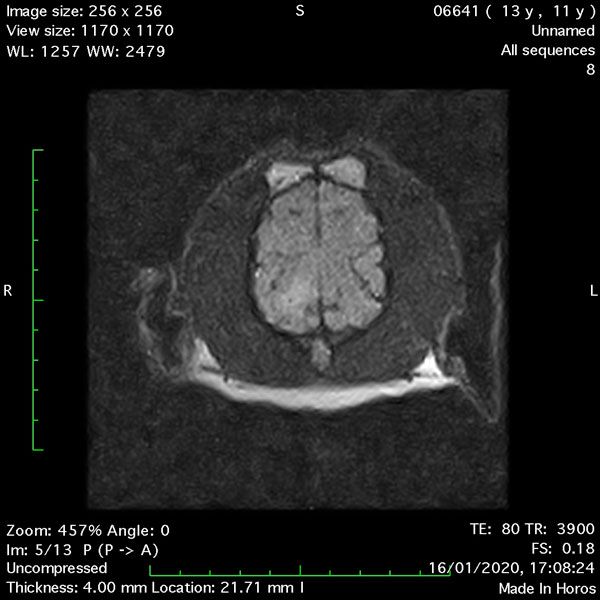

- Transverse T1 – Spin Echo T1 (Figure 1);

MRI images were viewed in DICOM format (Digital Imaging and Communications in Medicine) (Figures 1-7) and assessed in-house under the guidance of a board-certified radiologist. The series were evaluated for changes in intensity in the T1- and T2-weighted sequences (T1w and T2w, respectively). There was a 4mm x 7mm x 7mm intra-axial, wedge-shaped hyperintense reasonably-well demarcated region in the right cerebrum visible in the T2w images (Figures 2-3). This was consistent with a focal infarct. No contrast enhancement, anatomical abnormality nor space occupying lesion was noted in the T1w sequences (Figure 1, Figure 4). There was no observed pathology on assessment of the FLAIR images (Figure 5).

Figures 1-7: Images obtained with MRI depicted in sequential order and assessed under the guidance of a board-certified radiologist in-house.